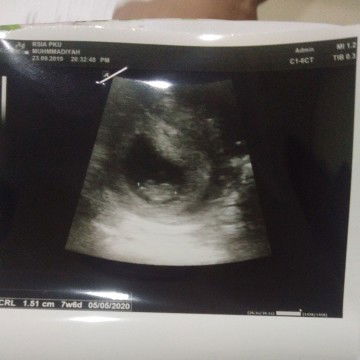

alhamdulillah

Usg usia kehamilan 7w6d Kalo bedasarkan hpht 8w3d But alhamdulillah calon bayinya sudah terlihat dan detak jantungnya bagus,, Hpl Awal Mei 05-05-2020 Sebelumnya usg 5w belum keliatan calon babby baru kantungnya aja, tp setelah 2 minggu kemudian udah ada calon babbynya dan sudah terdeteksi detak jantung bayinya